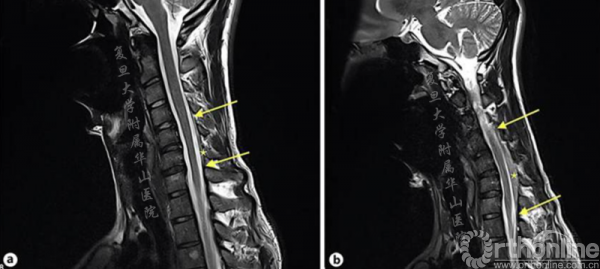

行3T的颈椎磁共振成像(MRI)检查,显示颈部伸直,C5-6节段脊髓萎缩。颈部屈曲时,后方硬膜有前移位,后部硬膜空间扩大,硬膜和椎板间距离增加(从1.4~6.1mm)(图2和3)。

图2.MRI颈椎矢状位T2加权成像,a中立位,显示颈脊髓变直,C5-6水平节段的脊髓变细,可能反映脊髓萎缩;b过曲位,显示后硬膜前移,后硬膜空间扩大,“硬膜椎板间距离增加,从到1.4~6.1mm(*),脊髓长度增加()